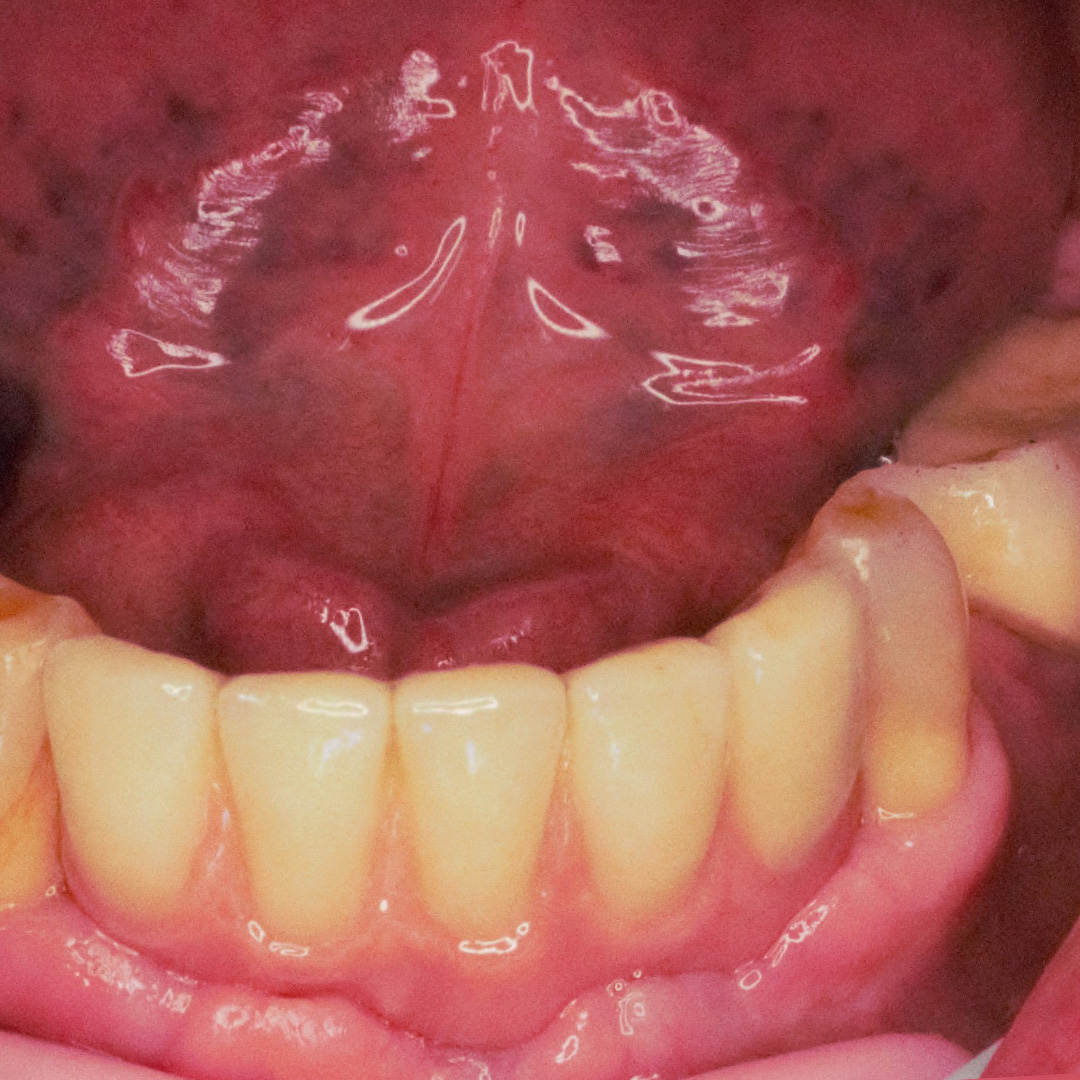

К нам в клинику обратился пациент с жалобой на частично отсутствующие зубы на нижней челюсти.

В ходе лечения были проведены следующие работы:

- санация полости рта;

- установка 3 имплантов системы Alpha Bio;

- изготовление и установка металлокерамических коронок на имлантах системы Alpha Bio.